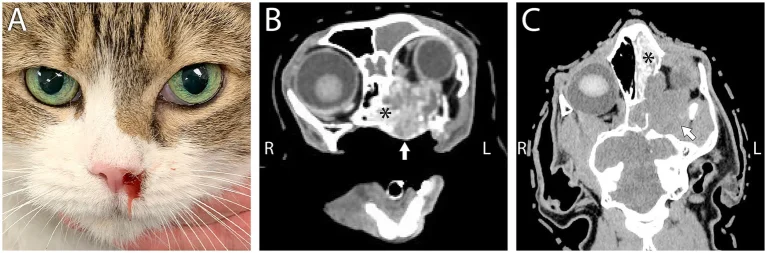

Dưới góc độ y khoa chuyên sâu, sự kết hợp giữa biến dạng sống mũi và lồi nhãn cầu là dấu hiệu kinh điển của một cuộc xâm lăng sinh học tàn bạo mang tên: Nhiễm nấm toàn thân Cryptococcosis.

Mèo bị lồi mắt đi kèm gồ sống mũi là do sự phát triển của một khối u nấm khổng lồ chèn ép từ sâu bên trong sọ não. Việc tự ý dùng kim chích nặn mủ tại nhà là vô tác dụng và cực kỳ nguy hiểm. Thú cưng cần được chẩn đoán tế bào học và bắt đầu phác đồ kháng nấm đặc hiệu lập tức trước khi dây thần kinh thị giác bị đứt gãy.

2. Exophthalmos: Khi khối u nấm “bứng” nhãn cầu ra ngoài

Sự tàn phá của nấm Cryptococcus không dừng lại ở khoang mũi. Với khả năng ăn mòn cả xương sọ, các mô nấm tiếp tục bành trướng và xâm lấn sâu vào không gian chật hẹp phía sau hốc mắt (được gọi là Retrobulbar space).

Sự xuất hiện của một khối u sau nhãn cầu (Retrobulbar mass) vô hình trung biến thành một chiếc đòn bẩy khổng lồ từ bên trong. Nó tàn nhẫn đẩy toàn bộ con ngươi của mèo lồi hẳn ra ngoài khỏi quỹ đạo thông thường – tình trạng này được gọi là Đẩy lồi nhãn cầu (Exophthalmos). Khi mắt bị lồi quá mức, mí mắt không thể nhắm kín để cung cấp màng phim nước mắt bôi trơn, làm tăng cực độ rủi ro loét giác mạc chó mèo nung chảy nhãn cầu nếu không được can thiệp giữ ẩm y khoa.